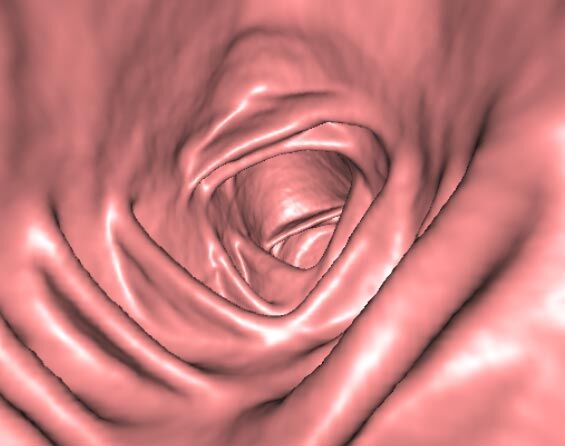

• Virtuelle Kolonographie zur Darstellung des Dickdarmes z. B. bei Kontraindikation zur Darm-Spiegelung oder nur unvollständig durchführbarer Koloskopie.